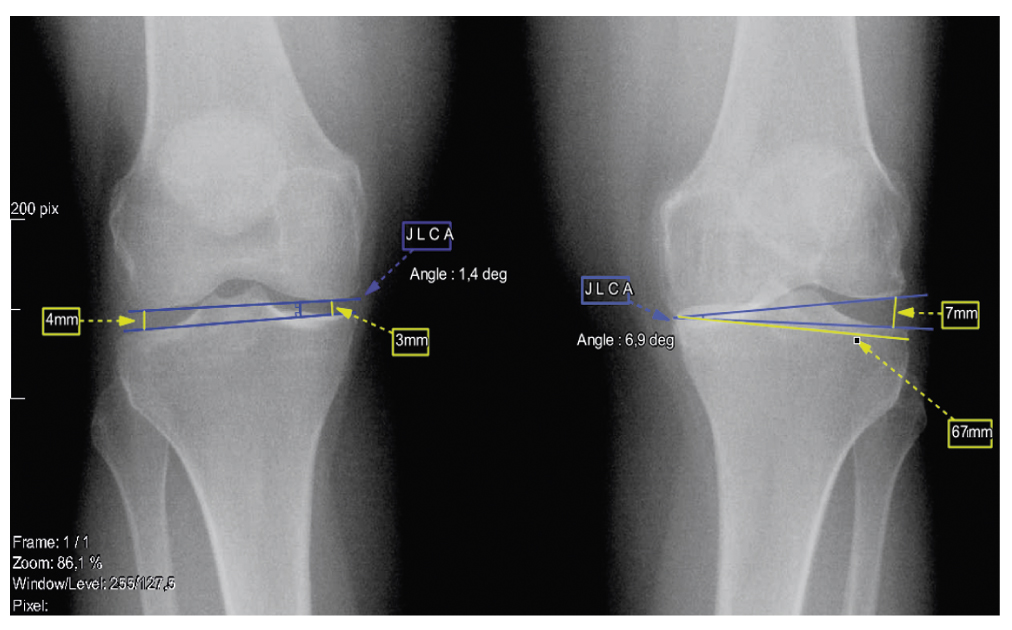

В представленном клиническом случае при планировании не была учтена должным образом недостаточность связочного аппарата коленного сустава. На первичных топограммах видно, что суставная щель неравномерна. Увеличение высоты суставной щели с латеральной стороны свидетельствует о наружной несостоятельности связочного аппарата коленного сустава. Разница в высоте суставной щели между относительно здоровой правой и левой нижней конечностью составляла 4 мм (рис. 5).

Рис. 5. Расчет степени варусной деформации за счет мягких тканей. / Fig. 5. Calculation of the varus deformation degree due to soft tissues.

Для правильной оценки влияния угла наклона суставных поверхностей коленного сустава (joint line convergence angle, JLCA) и оценки нестабильности связочного аппарата необходимо выполнять рентгенограмму коленного сустава в положении 45° сгибания коленного сустава по Розенбергу. Расчет величины варусной деформации из-за недостаточности связочного аппарата возможен с использованием следующей формулы: β=(C·(∆S))/TW, где ∆S — разница между высотой суставной поверхности компартмента сустава в норме и патологии, TW — ширина суставной поверхности плато большеберцовой кости, C — постоянная величина, равная 76,4 [13]. В данном случае ∆S=4, но по данным топограммы стоя, без сгибания коленного сустава, TW=67 мм, значит, β=4,5°. Так как несостоятельность медиальной или латеральной коллатеральной связки оказывает значительное влияние на стабильность коленного сустава, важно учитывать величину нестабильности за счет связочного аппарата для правильной коррекции оси конечности [14]. В данном случае реальная варусная деформация за счет геометрии кости, повреждения хряща и медиального мениска составляла порядка 5,5°. Значит, коррекция MPTA на 12,6° скорректировала бы HKA до 8,4° вальгусной деформации, но из-за возможной нестабильности медиальной коллатеральной связки и перелома в месте центра вращения остеотомии данная деформация увеличилась до 11,2° вальгуса.